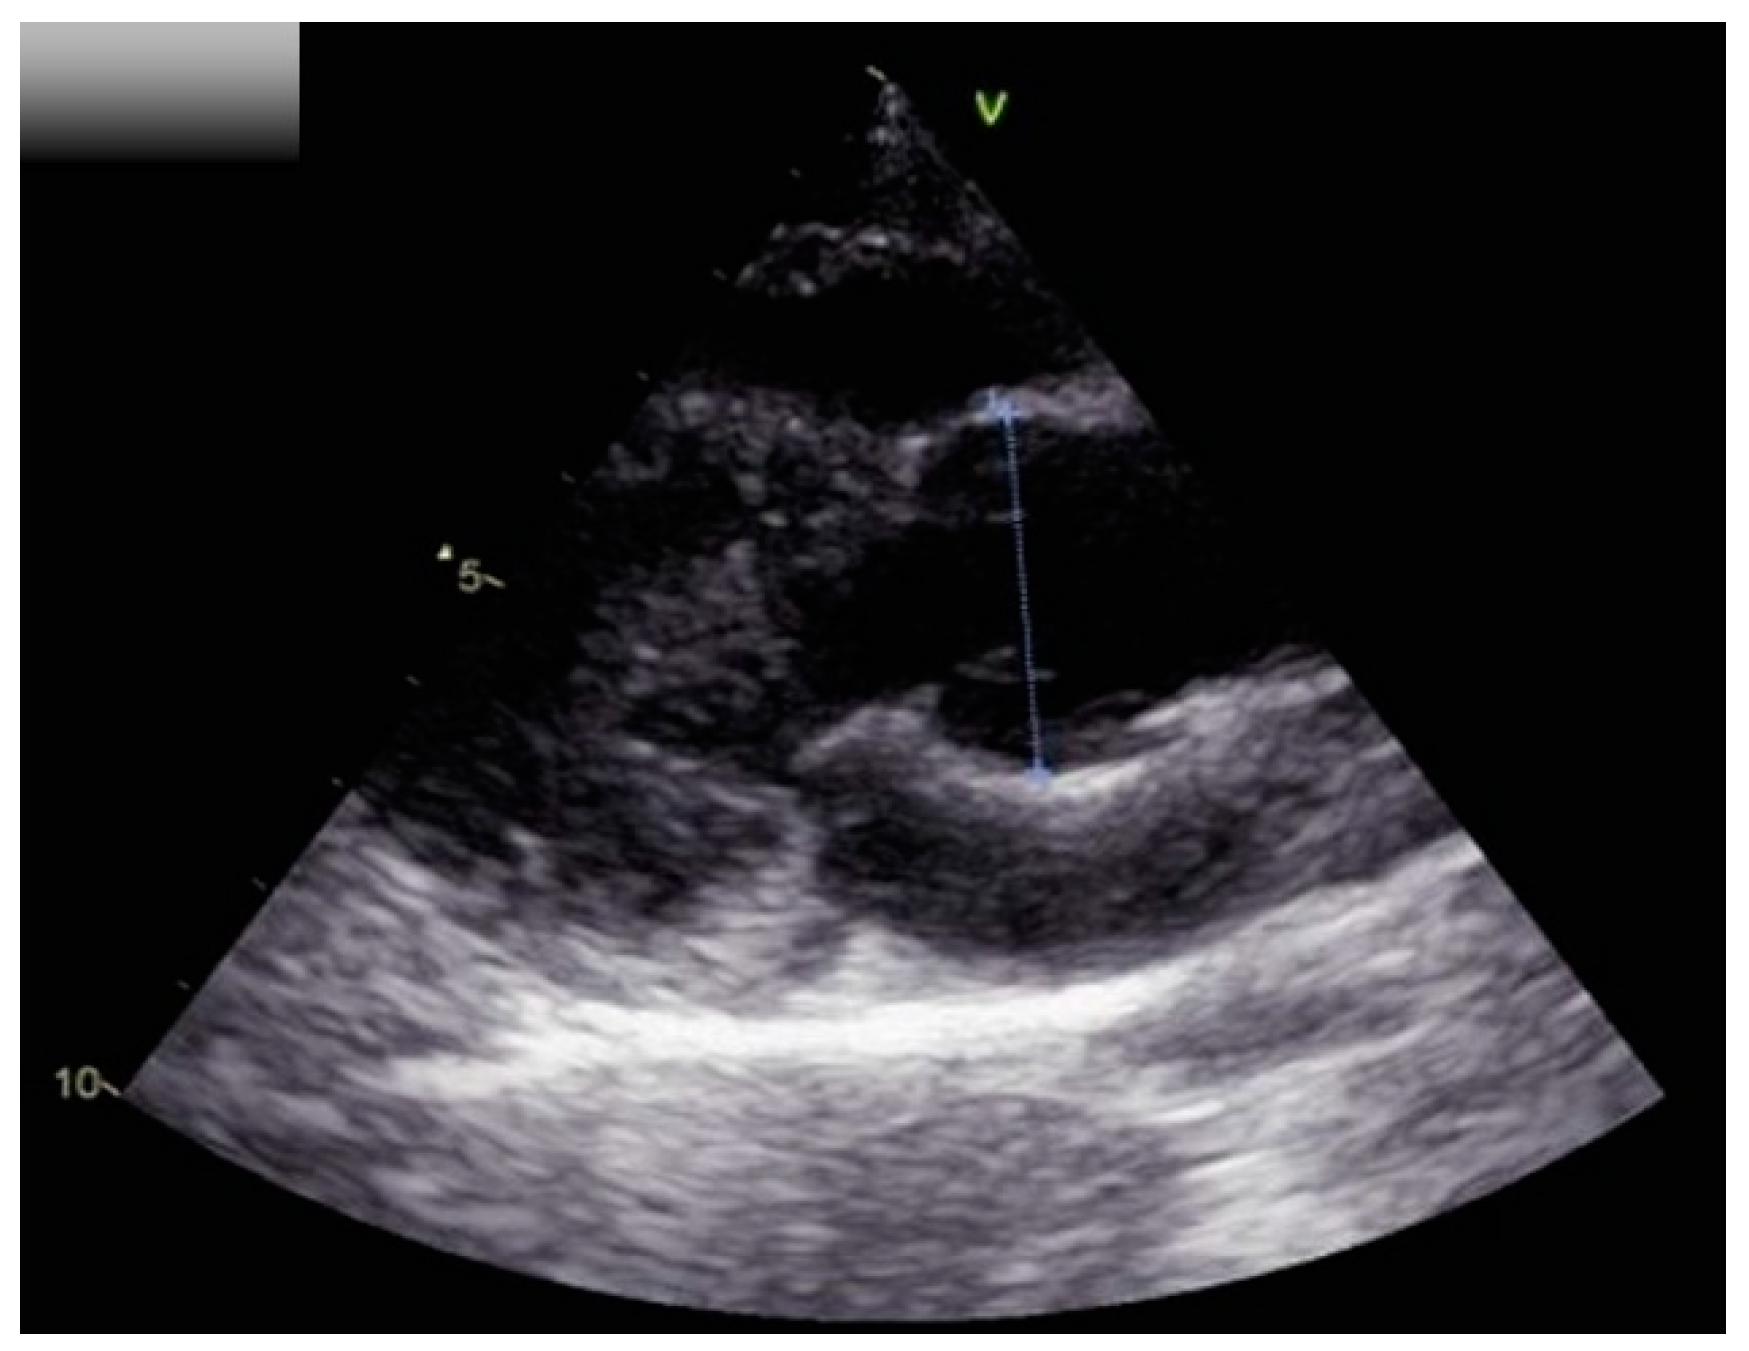

| Aortic root size (Z-score) | 29 mm (2.5) | 25 mm (0.7) |